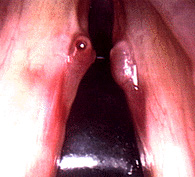

Close up of a vocal cyst

The image to the right shows a vocal fold cysts in a soprano who had significant hoarseness. This picture was taken with a stroboscopic light source through a flexible fiberoptic scope. The vocal folds are therefore "frozen" in time at the point of closure. Note that the folds cannot close completely due to the cyst. This cyst was removed surgically and the voice returned to normal.